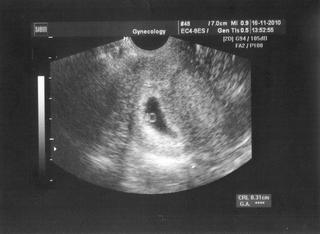

@pigy Ahojky, dopadla jsem dobře. Dle MS jsem v 6tt+6 a máme srdíčko.